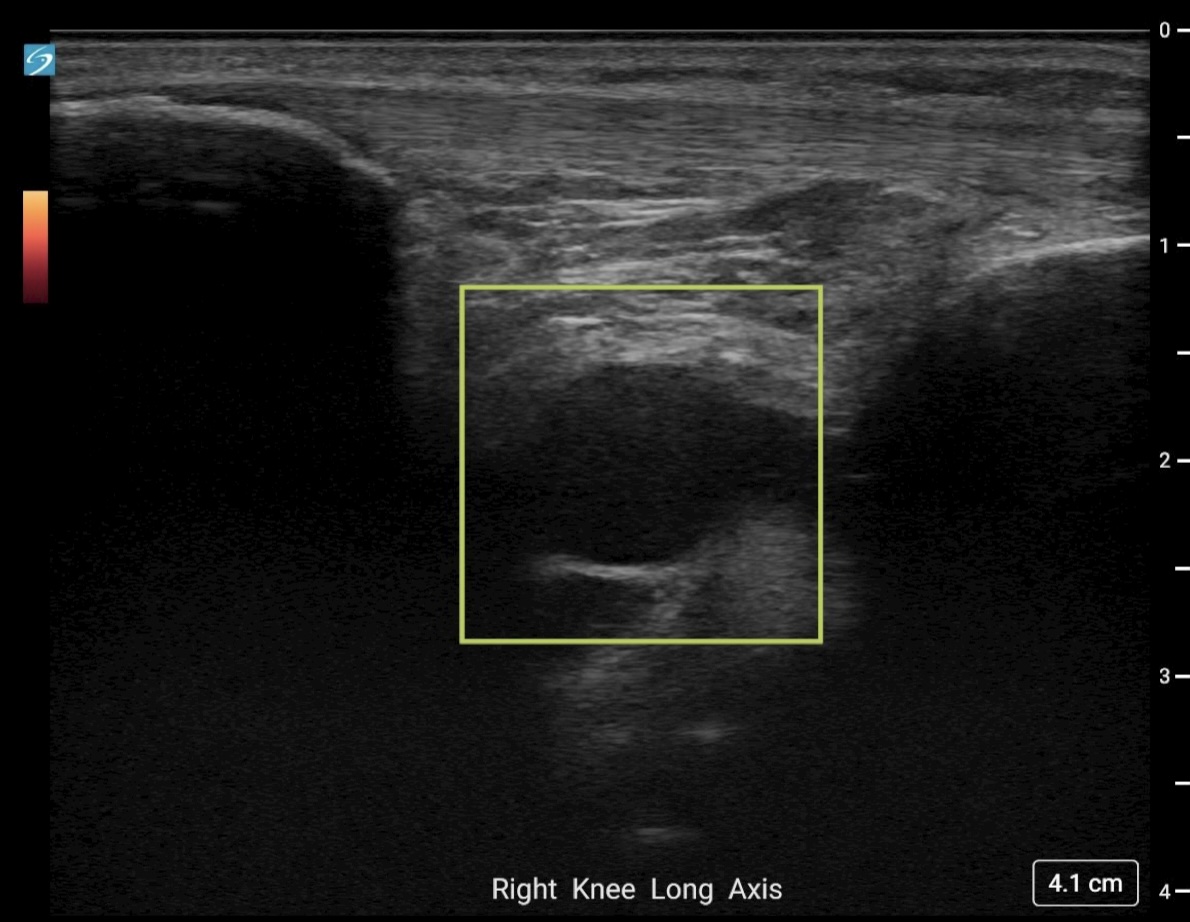

Image Interpretation: An anechoic, well-circumscribed, well-demarcated mass was noted deep to the infrapatellar fat pad. This measured 2.02 cm x 1.08 cm x 1.72 cm. No color Doppler flow was noted and the structure remained noncompressible when pressure was applied. A separate, smaller, anechoic mass was noted deeper to this structure and likely communicated with it. Findings were consistent with a multiloculated cyst of intra-articular origin.